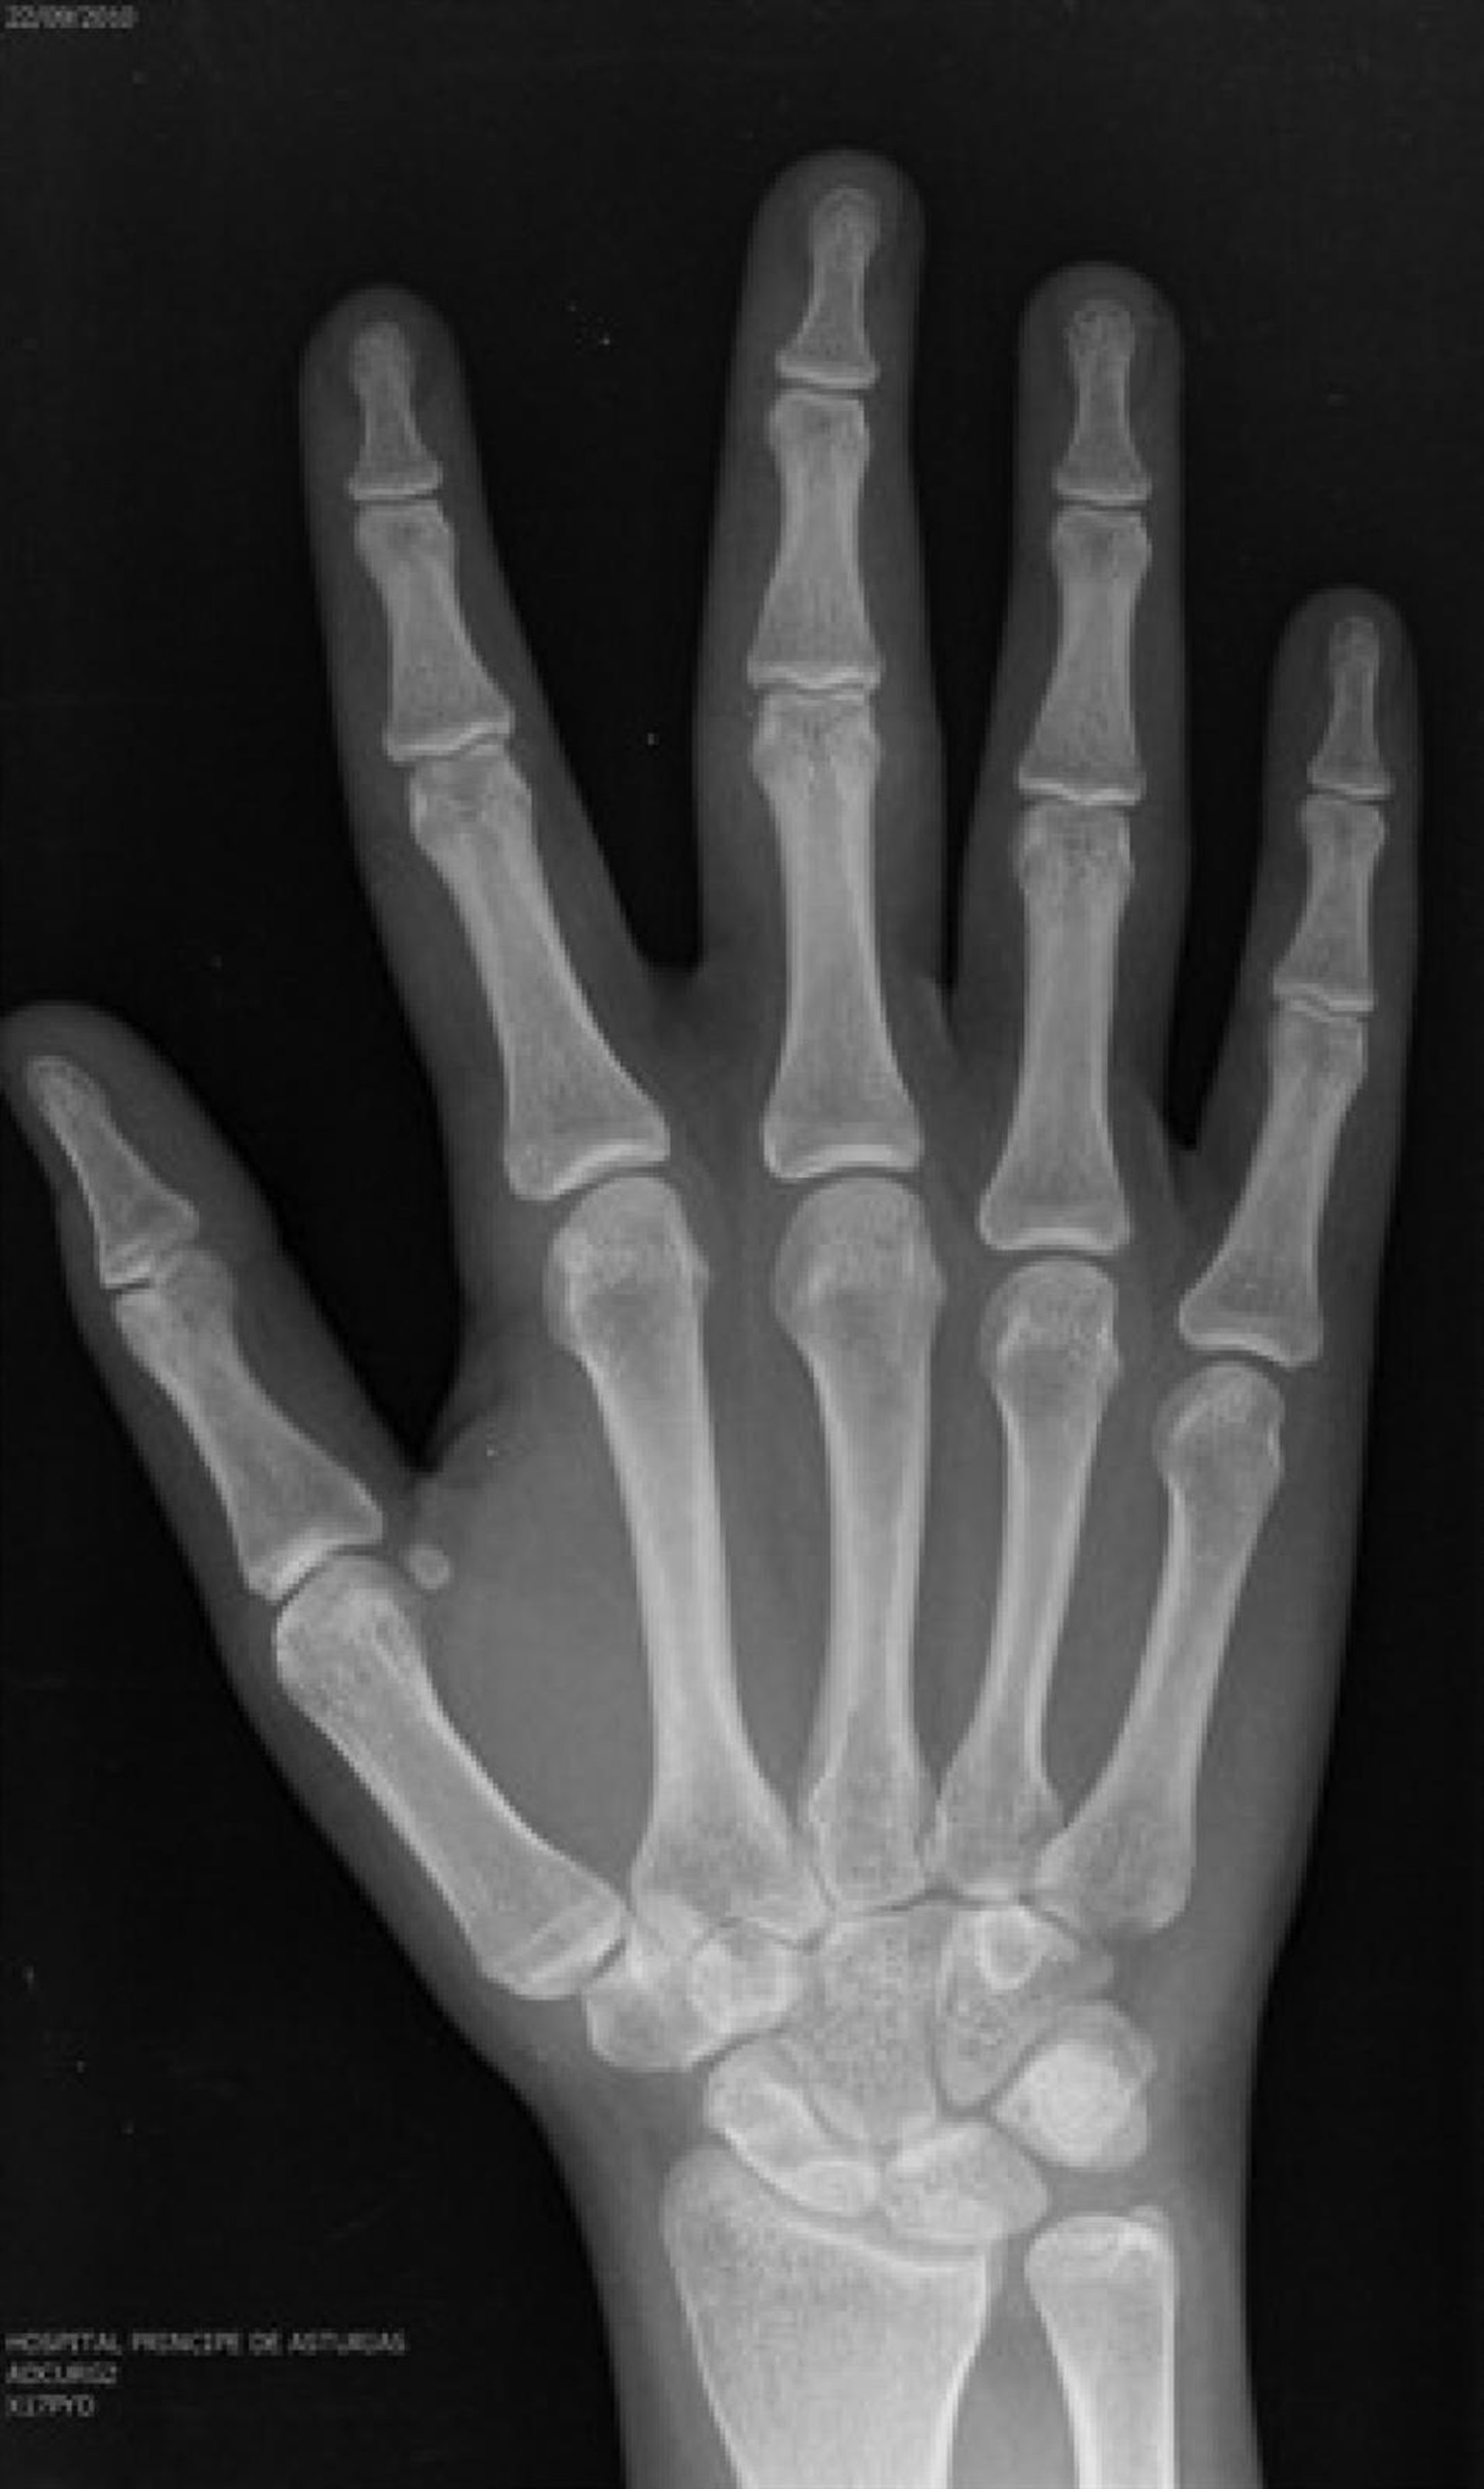

Prueba Radiológica Para Determinar La Edad

Un inmigrante puede ser adulto o adolescente en función del lugar donde le examinen, según denuncia en un informe el Defensor del Pueblo, en el que expone el caso de un joven al que sometieron a pruebas radiológicas para determinar la edad ósea en hospitales de Valencia, Andalucía y Madrid, siendo los resultados diferentes en un intervalo de dos semanas, o el de una mujer subsahariana de raza negra declarada mayor de edad en menos de 24 horas siguiendo criterios para varones blancos.

La falta de rigor científico en los procedimientos para determinar la edad de los menores extranjeros no acompañados es una de las conclusiones de este trabajo, en el que se advierte de que en muchos casos les someten exclusivamente a una única prueba, cuando los expertos indican que el proceso de estimación debe ser el resultado del trabajo de diversos especialistas --radiólogos, forenses, médicos y psicólogos, entre otros--.